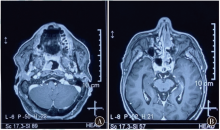

多发鼻腔鼻窦及口咽部黏膜恶性黑色素瘤1例及文献复习

恶性黑色素瘤是一种由异常黑色素细胞过度增生引发的高度恶性肿瘤,好发于皮肤黏膜组织,而鼻腔鼻窦及口咽部黏膜的恶性黑色素瘤病例极为罕见。现报道1例多发鼻腔鼻窦及口咽部黏膜恶性黑色素瘤的患者,通过复习相关文献,对恶性黑色素瘤的诊断、病理特征及治疗等方面展开探讨。